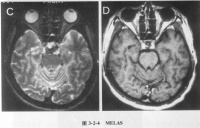

4.脑影像学检查

随着脑影像技术的开展与提高,近10年已有许多有关CT及MRI检查本病的报道。我国曾报道对100例氧化碳中毒患者于急性期和出现迟发脑病时进行颅脑CT检查见主要异常为双侧大脑皮质下白质及苍白球或内囊出现大致对称的密度减低区,后期可见脑室扩大或脑沟增宽,异常率分别为41.2%和87.5%脑CT无异常者预后较好,有CT异常者其昏迷时间大都超过48小时。但迟发脑病早期并无CT改变上述CT异常一般在迟发脑病症状出现2周后方可查见,故不如脑诱发电位及脑电图敏感。急性期CT已显示大脑皮质持下白质异常的患者其恢复远较迟发脑病有白质异常者为差,提示两类患者的白质病理改变不同,前者可能兼有髓鞘轴索的损伤后者可能多仅为髓鞘的脱失。MRI在显示一氧化碳中毒脑部病变方面优于CT,二者皆有利于与脑部其他疾病的鉴别诊断